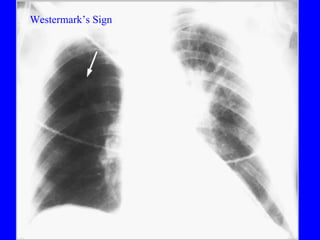

Diagnosis CXR Usually reveals a non specific abnormality.  14% normal Classic abnormalities include: Westermark’s Sign - focal oligemia Hampton’s Hump - wedge shaped density Enlarged Right Descending Pulmonary Artery (Palla’s sign)

PE Westermark’s Sign

Diagnosis CXR Usuallyreveals a non specific abnormality. 14% normal Classic abnormalities include: Westermark’s Sign - focal oligemia Hampton’s Hump - wedge shaped density Enlarged Right Descending Pulmonary Artery (Palla’s sign)